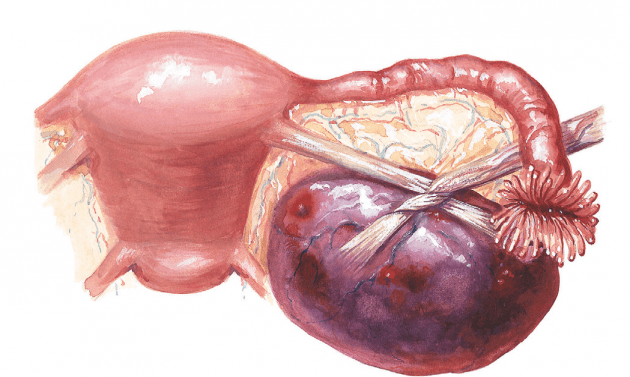

Методы лечения кистомы яичника

Не зависимо от типа кистомы яичника, ее размера, наличия характерных клинических симптомов и отсутствия таковых, необходимо проведение хирургического вмешательства. Это единственный способ лечения, позволяющий предотвратить возможную малигнизацию кистомы, ее чрезмерный рост и ассоциированное с ним нарушение функционирования тазовых органов. При проведении оперативного вмешательства квалифицированный специалист выполняет удаление доброкачественной опухоли, предпринимает меры к установлению ее природы и исключает ее озлокачествление. Объем необходимого вмешательство определяется врачом на основе индивидуального подхода. Он зависит, прежде всего, от вида кистомы яичника, ее параметров и размера, возрастом пациентки и ее желанием к реализации в дальнейшем репродуктивной функции. Хирургическое вмешательство при кистоме яичника может выполняться посредством следующих методик:

С целью установления объема операции проводится неотложное гистологическое исследование тканей новообразования. При лечении серозных кистом у женщин, моложе 40 лет, имеющих желание к реализации репродуктивной функции, при выполнении операции стараются максимально обеспечить сохранение здоровой ткани яичника. С этой целью проводится кистэктомия, в ходе которой удаляется опухоль и при этом максимально сохраняется овариальная ткань. Папиллярные и муцинозны доброкачественные новообразования удаляют исключительно вместе с придатком (оофорэктомия). В период постменопаузы для лечения кистомы яичника рекомендуется удаление матки с яичниками посредством методики пангистерэктомии. При разрыве капсулы кистомы, а также при перекруте ножки операция проводится в экстренном порядке.